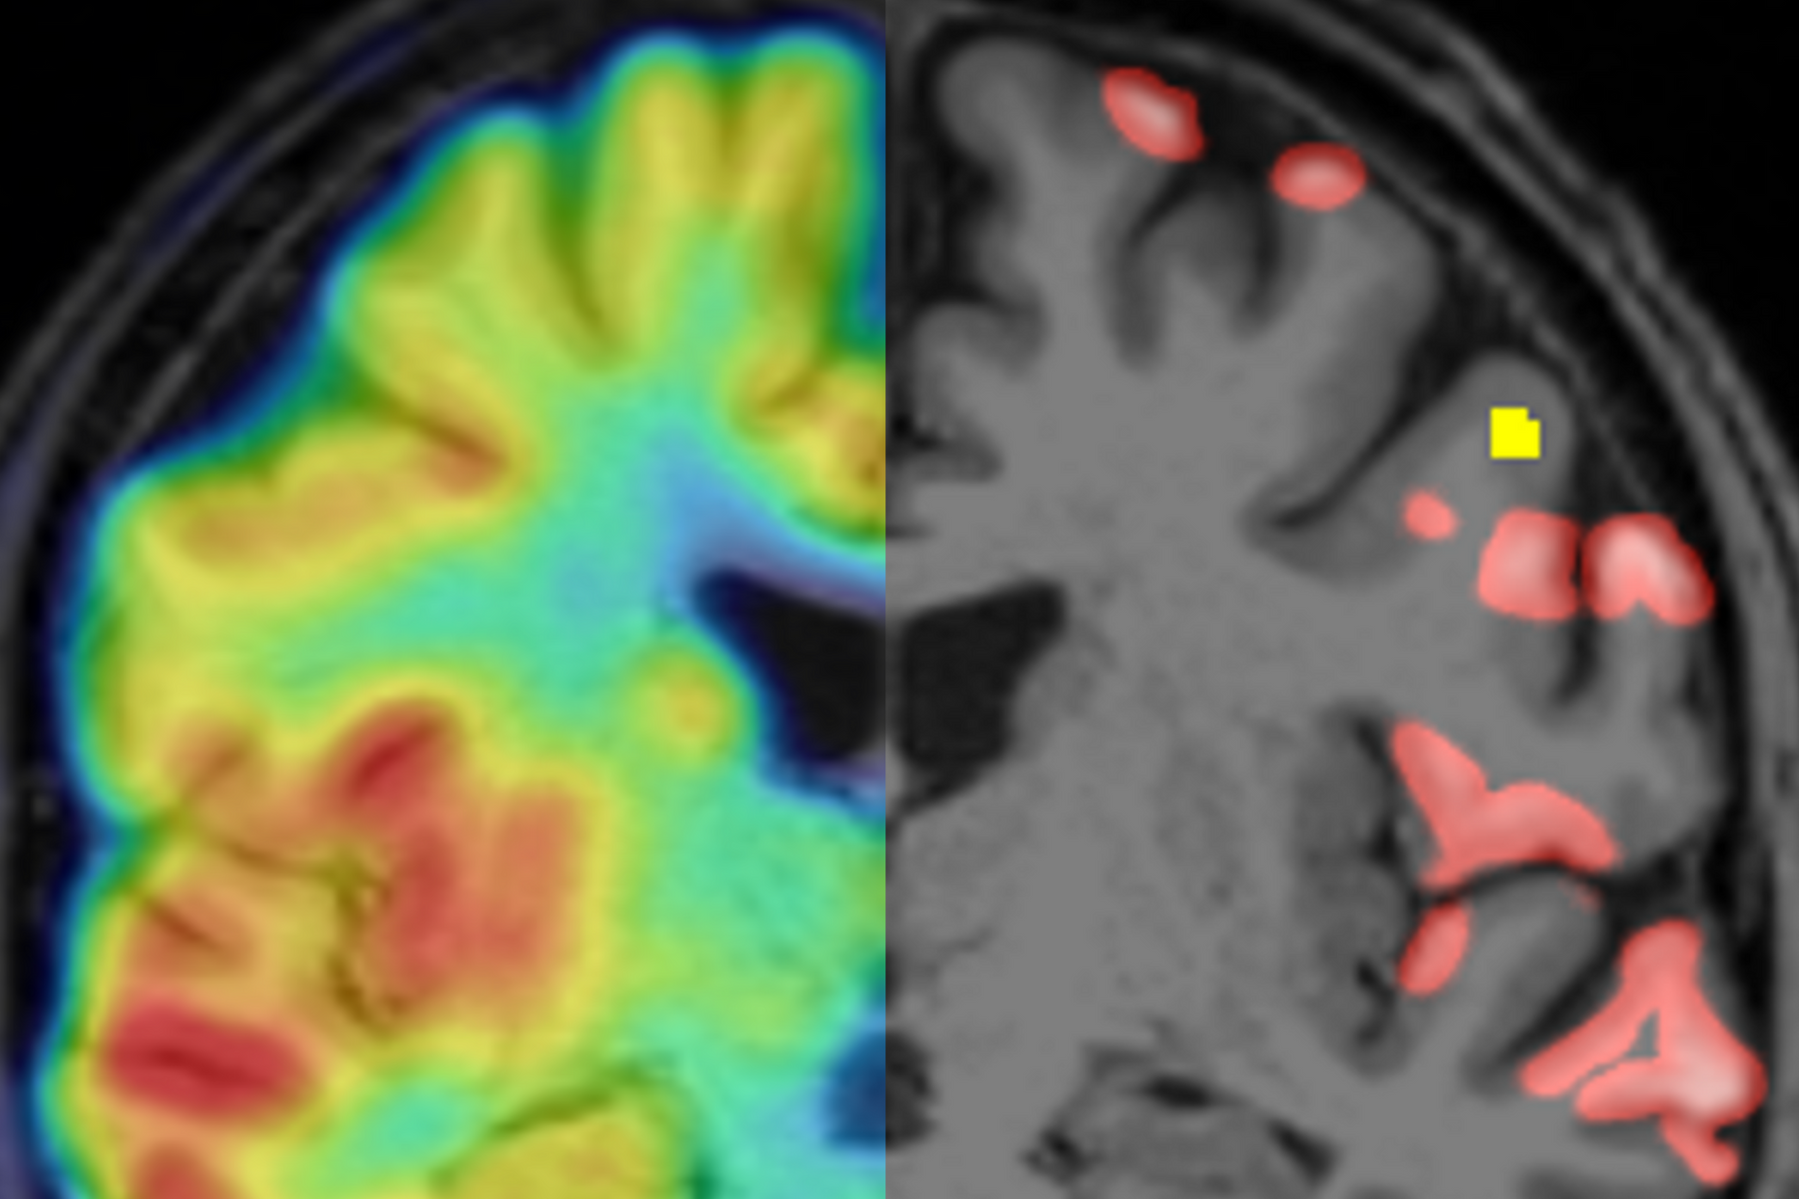

Überlagerung von Synapsen PET und MRT (links) und segmentierte Regionen mit cortikalen Läsionen in der MRT (gelb) sowie reduzierter Synapsendichte (rot)

Multiple Sklerose: Nachweis veränderter grauer Substanz mittels PET

In Deutschland leiden etwa 250.000 Menschen an der Multiplen Sklerose, kurz MS genannt. Es handelt sich um eine Autoimmunerkrankung, bei der die Körperabwehr Strukturen des Zentralen Nervensystems angreift. Die Attacken führen auch zu Veränderungen in der grauen Substanz im Gehirn - die Masse der Nervenzellkörper und Nervenzellverbindungen (Synapsen), die sozusagen unser “Rechenzentrum” bilden. Bislang gibt es keine Methode, um diese krankhaften Läsionen der grauen Substanz verlässlich und aussagekräftig nachzuweisen. Nun aber haben Forschende des LMU Klinikums erstmals gezeigt, dass sich mit der Positronen-Emissionstomografie (PET) der Synapsenverlust in den MS-Läsionen der Großhirnrinde abbilden lässt. Langfristig wollen die Forschenden um Prof. Dr. Matthias Brendel von der Klinik und Poliklinik für Nuklearmedizin und Prof. Dr. Martin Kerschensteiner vom Institut für Klinische Neuroimmunologie das Verfahren so entwickeln, “dass wir damit die Therapie steuern können”, wie Brendel sagt.

Kann ein anderes bildgebendes Verfahren, die PET, helfen? Dazu müsste man ein Protein der Nervenzellen finden, das sich einerseits mit diesem Verfahren nachweisen lässt und andererseits wertige Aussagen über die Dichte der Neuronen bzw. ihrer Synapsen liefert. In einer Serie von Experimenten bewies das Kerschensteiner-Labor zunächst, dass das Protein SV2A ein geeigneter Marker für die Synapsendichte bei MS ist. Anschließend hat das Team Mäusen, bei denen eine MS-ähnliche Entzündung der Hirnrinde ausgelöst wurde, eine schwach radioaktive Substanz gespritzt, die gezielt an SV2A andockt. Das strahlende Signal wird dann vom PET-Gerät erkannt. Zur Kontrolle und zum Vergleich wurden die Synapsendichten in denselben Läsionen mit etablierten Methoden gemessen. „So konnten wir zeigen, dass die mit PET-Bildgebung gemessenen Synapsendichten aussagekräftige Ergebnisse erzeugen“, erklärt Kerschensteiner, „bestätigt hat sich das auch in einer anschließenden Untersuchung mit gut 30 MS-Patienten.“